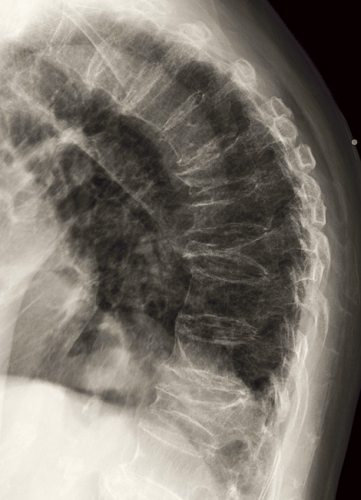

Det är därför märkligt att kopplingen mellan kastration av män och ökad risk för osteoporosfraktur inte kommit i strålkastarljuset förrän under de allra senaste åren. Ryggsmärtor hos prostatacancerpatienter som beror på osteoporotiska kotkompressioner (Figur 1) missbedöms sannolikt ofta som orsakade av metastaser. Läkartidningens temanummer om osteoporos år 2006 (40/2006) innehöll inte en enda rad om kastrationsbehandling vid prostatacancer. Inte heller Läkemedelsverkets eller SBU:s senaste sammanställningar och rekommendationer nämner denna patientgrupp. I Socialstyrelsens nationella riktlinjer för prostatacancersjukvården från år 2007 står att kastration medför osteoporos och att behandling med bisfosfonater kan motverka denna, men några riktlinjer för vilka patienter som ska få sådan behandling kan inte utläsas [3].